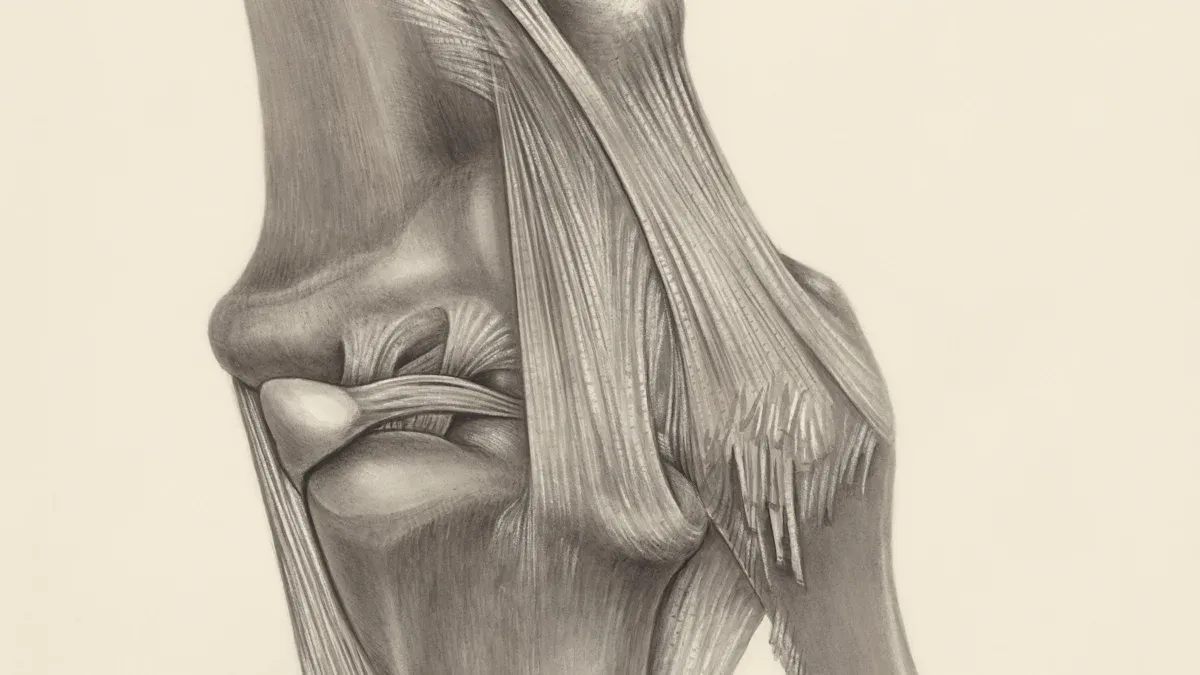

When you see a chiropractor for cervical vertigo chiropractic, you get spinal adjustments first. These adjustments help put your neck and spine back in place. If your vertebrae move out of position, they can press on nerves and cause balance problems. A chiropractor uses gentle moves to guide your neck into the right spot. This helps your nerves send clear messages between your brain and body.

Upper cervical chiropractic care focuses on the top two bones in your neck, called the atlas (C1) and axis (C2). These bones protect your brainstem, which controls balance and movement. If these bones move out of place, they can mess up nerve signals and cause vertigo.

Soft tissue therapy works on the muscles and tissues around your neck and shoulders. Tight or hurt muscles can make vertigo worse. A chiropractor uses hands-on techniques to relax these muscles and help your neck move better.

This therapy helps your body know where it is in space, which is called proprioception. When your proprioception gets better, you feel more balanced and less dizzy. Soft tissue therapy also works well with spinal adjustments for long-term relief.